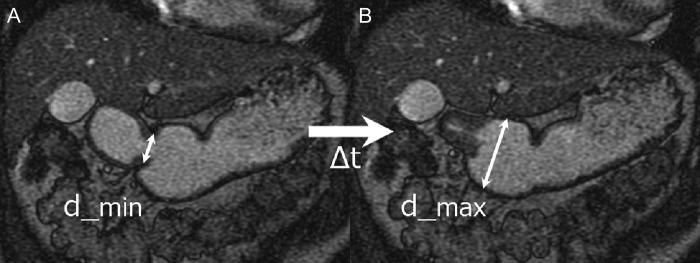

This study assessed abdominal organ motion induced by gastroduodenal motilities in volunteers during fasting and postprandial states, using cine magnetic resonance imaging (cine-MRI). Thirty-five volunteers underwent cine-MRI while holding their breath in the fasting and postprandial states. Gastric motility was quantified by the amplitude and velocity of antral peristaltic waves. Duodenal motility was evaluated as the change of duodenal diameter. Abdominal organ motion was measured in the liver, pancreas and kidneys. Motion was quantified by calculating maximal organ displacement in the left-right, antero-posterior and caudal-cranial directions. Median antral amplitude and velocity in the fasting and postprandial states were 7.7 and 15.1 mm (P < 0.01), and 1.3 and 2.5 mm/s (P < 0.01), respectively. Duodenal motility did not change. Median displacement for all organs ranged from 0.9 to 2.9 mm in the fasting state and from 1.0 to 2.9 mm in the postprandial state. Significant increases in abdominal organ displacement in the postprandial state were observed in the right lobe of the liver, pancreatic head and both kidneys. Differences in the median displacement of these organs between the two states were all <1 mm. Although the motion of several abdominal organs increased in the postprandial state, the difference between the two states was quite small. Thus, our study suggests that treatment planning and irradiation need not include strict management of gastric conditions, nor the addition of excess margins to compensate for differences in the intra-fractional abdominal organ motion under different gastric motilities in the fasting and postprandial states.

本研究采用电影磁共振成像(cine-MRI)评估空腹和餐后志愿者胃十二指肠运动引起的腹部器官运动。35 名志愿者在空腹和餐后状态下屏气进行 cine-MRI。通过测量胃窦蠕动的振幅和速度来量化胃动力。通过十二指肠直径的变化来评估十二指肠动力。测量肝脏、胰腺和肾脏的腹部器官运动。通过计算左右、前后和头尾方向的最大器官位移来量化运动。空腹和餐后状态下胃窦的平均振幅和速度分别为 7.7mm 和 15.1mm(P<0.01)和 1.3mm/s 和 2.5mm/s(P<0.01)。十二指肠动力没有变化。所有器官在空腹状态下的平均位移为 0.9 至 2.9mm,在餐后状态下为 1.0 至 2.9mm。在餐后状态下,肝脏右叶、胰头和双肾的腹部器官位移显著增加。两种状态下这些器官的平均位移差异均<1mm。尽管在餐后状态下几个腹部器官的运动增加,但两种状态之间的差异相当小。因此,我们的研究表明,在计划治疗和进行放疗时,不必严格管理胃的情况,也不必增加额外的边界来补偿空腹和餐后不同胃动力状态下的分次内腹部器官运动差异。